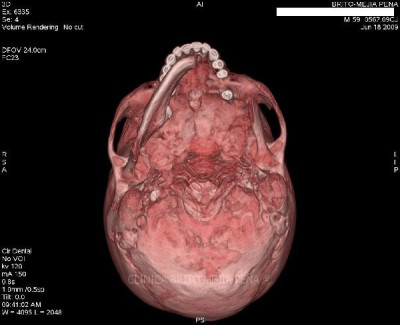

Cabeza y Cuello 2

Envíado por BMP Imágenes Diagnósticas

BMP Imágenes Diagnósticas